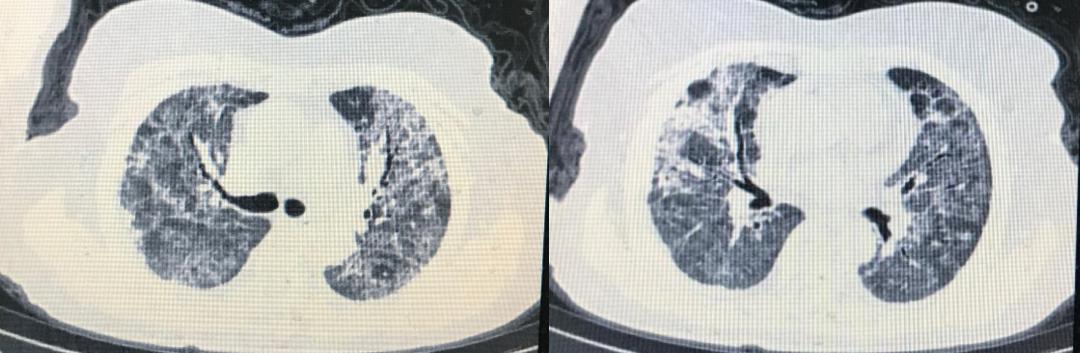

患者既往史有血糖增高,但并未作过处理,无高血压、肺病等疾病。患者入院查体的情况:T37.6℃,R32次/分,BP130/80,SPO2 76%(吸空气下),神志清,急性病容,呼吸急促,有三凹征。BMI 25。辅助检查结果为:血常规:中性粒细胞9.6×10^9/L,中性粒细胞90.4%,淋巴细胞4.3%,绝对值0.4×10^9/L,嗜酸粒细胞0.1%;白蛋白26.2g/L,BNP626pg/L,CRP37mg/L,D2聚体>8.0ug/ml,纤维蛋白原1.88g/L,肌钙蛋白29.5ng/L,LDH355U/L,血糖8.5mmol/L 。2月5日CT提示为双肺弥漫毛玻璃影,双侧少许胸腔积液(下图)。

2月20日,患者的HFNC改为储氧面罩(氧流量5-7升/min),SPO2 98%,呼吸频率22次/min。患者精神、食欲明显好转,停用静脉输液。2月20日及22日复查新冠病毒核酸2次阴性。2月21日复查CT明显好转。(见下图)